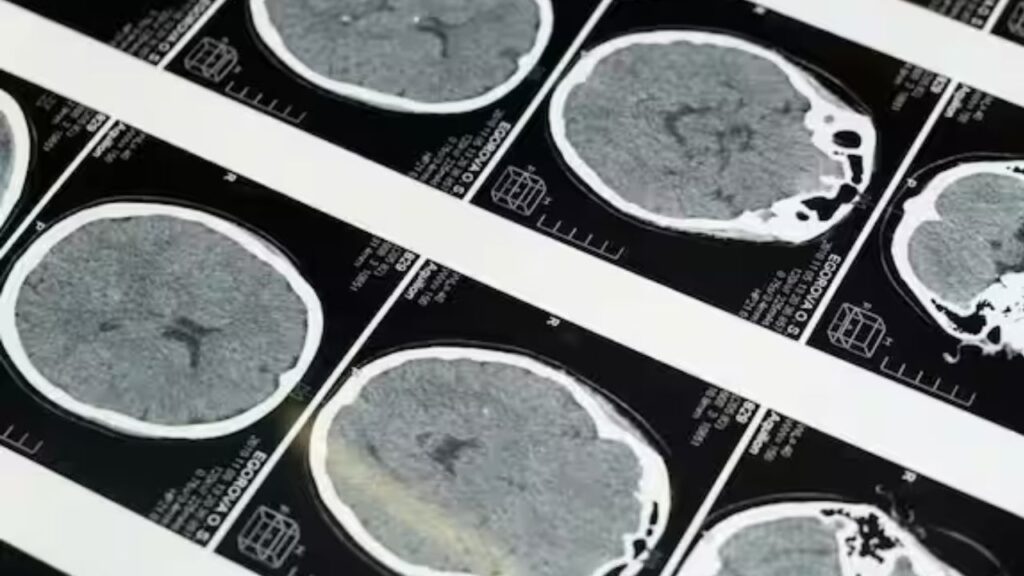

New Delhi: हाल ही में एक स्टडी में सामने आया है कि पुरुषों की तुलना में महिलाओं में अल्जाइमर का खतरा अधिक होता है। अल्जाइमर एक न्यूरोडीजेनेरेटिव बीमारी है, जो स्मृति और संज्ञानात्मक क्षमताओं में गिरावट का कारण बनती है। यह समस्या आम तौर पर वृद्ध लोगों में देखने को मिलती है, लेकिन शोध में यह खुलासा हुआ है कि यह पुरुषों की तुलना में महिलाओं में अधिक गंभीर रूप में पाई जाती है।

अल्जाइमर के रोग में मेमोरी लॉस, सोचने-समझने की क्षमता में कमी और भावनात्मक अस्थिरता जैसी समस्याएं सामने आती हैं। शोधकर्ताओं का कहना है कि उम्र बढ़ने के साथ इंसानों के दिमाग में ब्रेन एजिंग होती है, लेकिन यह प्रक्रिया पुरुषों और महिलाओं में अलग ढंग से होती है। हाल ही में PNAS में प्रकाशित एक अध्ययन में 17 से 95 साल की उम्र के लगभग 4700 वयस्कों के मस्तिष्क की जांच की गई। इसका उद्देश्य यह जानना था कि क्या ब्रेन एजिंग में लिंग का प्रभाव पड़ता है।

स्टडी के निष्कर्षों में पाया गया कि पुरुषों और महिलाओं दोनों में समय के साथ मस्तिष्क में बदलाव होते हैं, लेकिन दोनों के परिणाम समान नहीं हैं। विशेष रूप से पुरुषों में ब्रेन एजिंग के तेज संकेत मिले, जबकि महिलाओं में यह धीमी गति से होती दिखाई दी। पुरुषों के मस्तिष्क में पैराहिपोकैम्पल कॉर्टेक्स जैसे हिस्सों में तेजी से गिरावट देखने को मिली, जो स्मृति और भावनाओं के लिए जिम्मेदार हैं।

इसके विपरीत, महिलाओं में ब्रेन एजिंग के संकेत कम हिस्सों में देखे गए, लेकिन उनके दिमाग में ब्रेन वेंट्रिकल का आकार बढ़ता गया। शोधकर्ताओं ने कहा कि ब्रेन एजिंग में यह अंतर कई कारणों से हो सकता है, जिनमें मेटाबॉलिक फंक्शन, एपीजेनेटिक बदलाव, हार्मोनल परिवर्तन और अन्य जैविक कारक शामिल हैं।

अद्भुत रूप से, पुरुषों में ब्रेन टिश्यू तेजी से कम होते हैं और मस्तिष्क की संरचना छोटी होती जाती है, लेकिन इसके बावजूद अल्जाइमर जैसी स्मृति हानि की समस्या महिलाओं में अधिक देखी जाती है। इसका एक बड़ा कारण महिलाओं में हार्मोनल बदलाव हैं। मेनोपॉज, प्रेग्नेंसी और मासिक चक्र के दौरान हार्मोन स्तर में उतार-चढ़ाव मस्तिष्क की संरचना और कार्यप्रणाली पर असर डालते हैं।